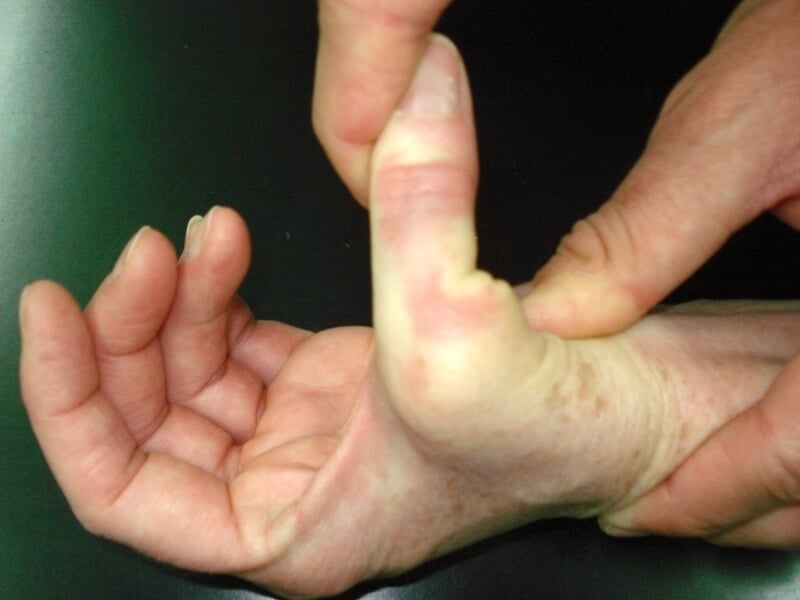

entorse mp pouce grave

Laxité importante d'une entorse grave de la MP du pouce

Les entorses des ligaments latéraux de la MP du pouce touchent surtout des patients jeunes et sportifs, en particulier les skieurs. Les conséquences peuvent être sérieuses. En cas d’entorse sévère, un traitement chirurgical est souvent nécessaire.